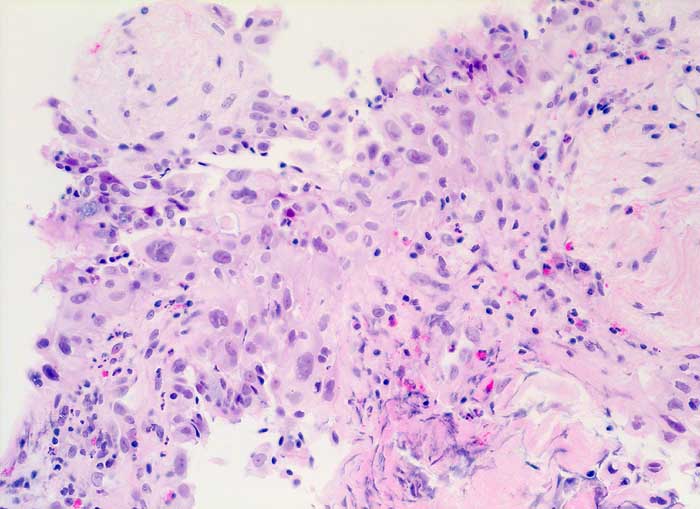

Strahleninduzierte Kernatypien

Nach Strahlentherapie eines mediastinalen Tumors oder eines Bronchuskarzinoms zeigen Bronchial- und Alveolarepithel ähnliche Kernveränderungen wie nach Zytostatikatherapie. Die Flimmerzellen haben unterschiedlich stark vergrösserte oft hyperchromatische und entrundete Kerne, sowie fragiles Zytoplasma. Der Nachweis von Flimmerhaaren und die erhaltene Kern-Zytoplasmarelation sprechen für reaktiv veränderte Bronchialepithelien.